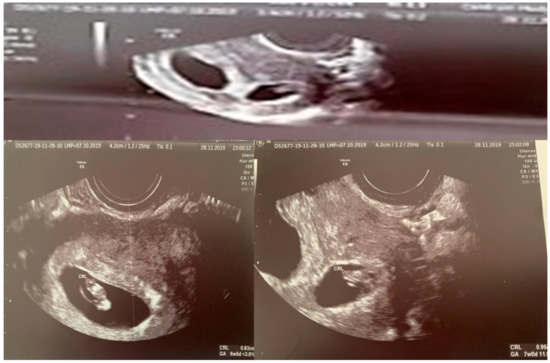

| Chorionicity | Dichorionic Diamniotic | |

| CRL(crown–rump length) (mm) | 49.2–11w5d | 51.30–11w6 |

| BPD (biparietal diameter) (mm) | 14.5–12w0 | 17.2–12w4d |

| FHR/min (fetal heart rate) | 160 | 161 |

| NT (mm) (nuchal translucency) | 1.42 | 1.2 |